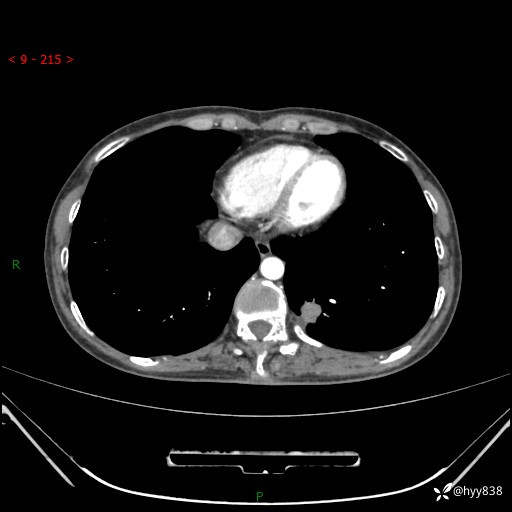

胸部CT平扫

增强动脉期+静脉期

各期CT值:48hu 65hu 76hu